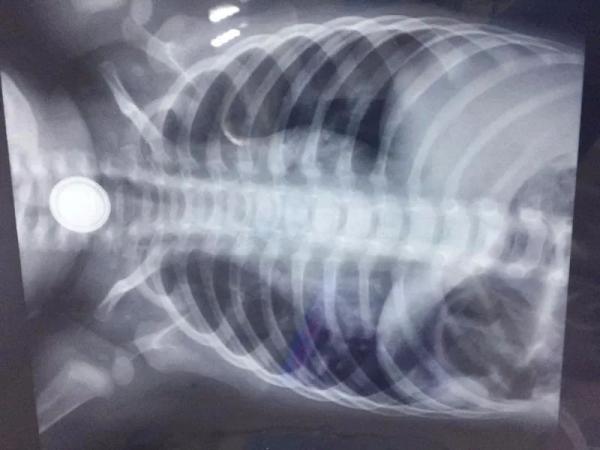

经过紧急拍片,医生证实确有一粒纽扣电池在孩子的食道上段,于是紧急入院,经多学科会诊后,医生决定在气管插管麻醉下,经内镜紧急取出纽扣电池。

X光片可看到被误吞的纽扣电池位置。